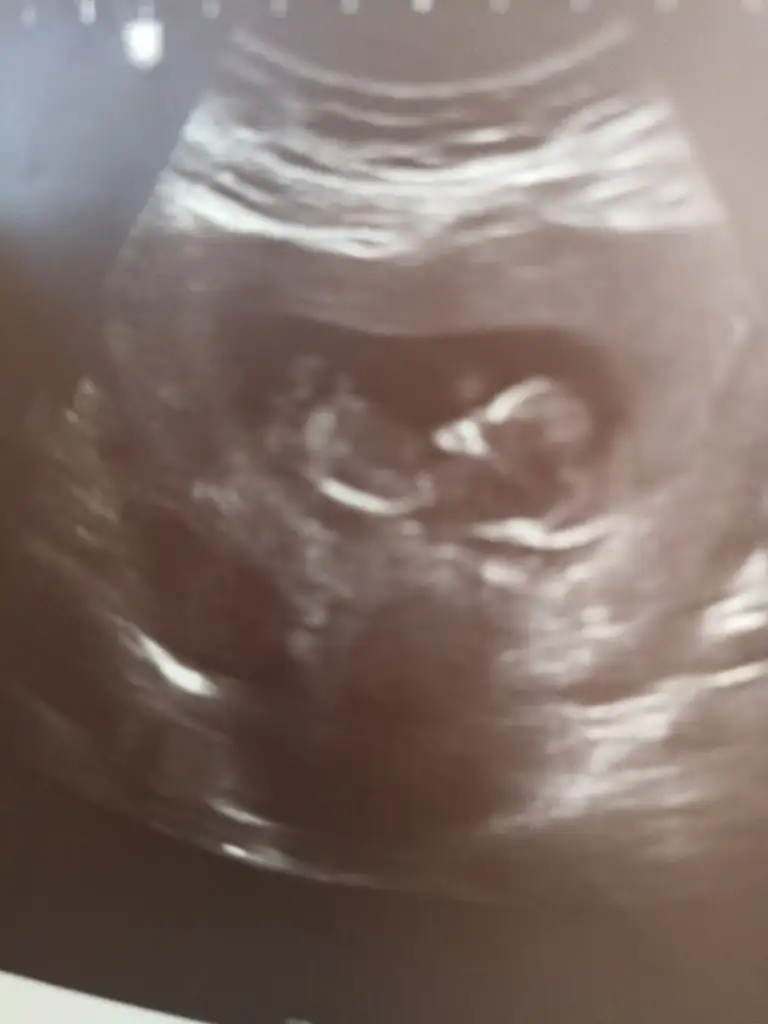

Canım benim ikisinide bildin buda arkadaşımın bunada bakarmisin🥰🥰

• IMG_20221020_133718.webp

IMG_20221020_133718.webp

23,8 KB · Görüntüleme: 102